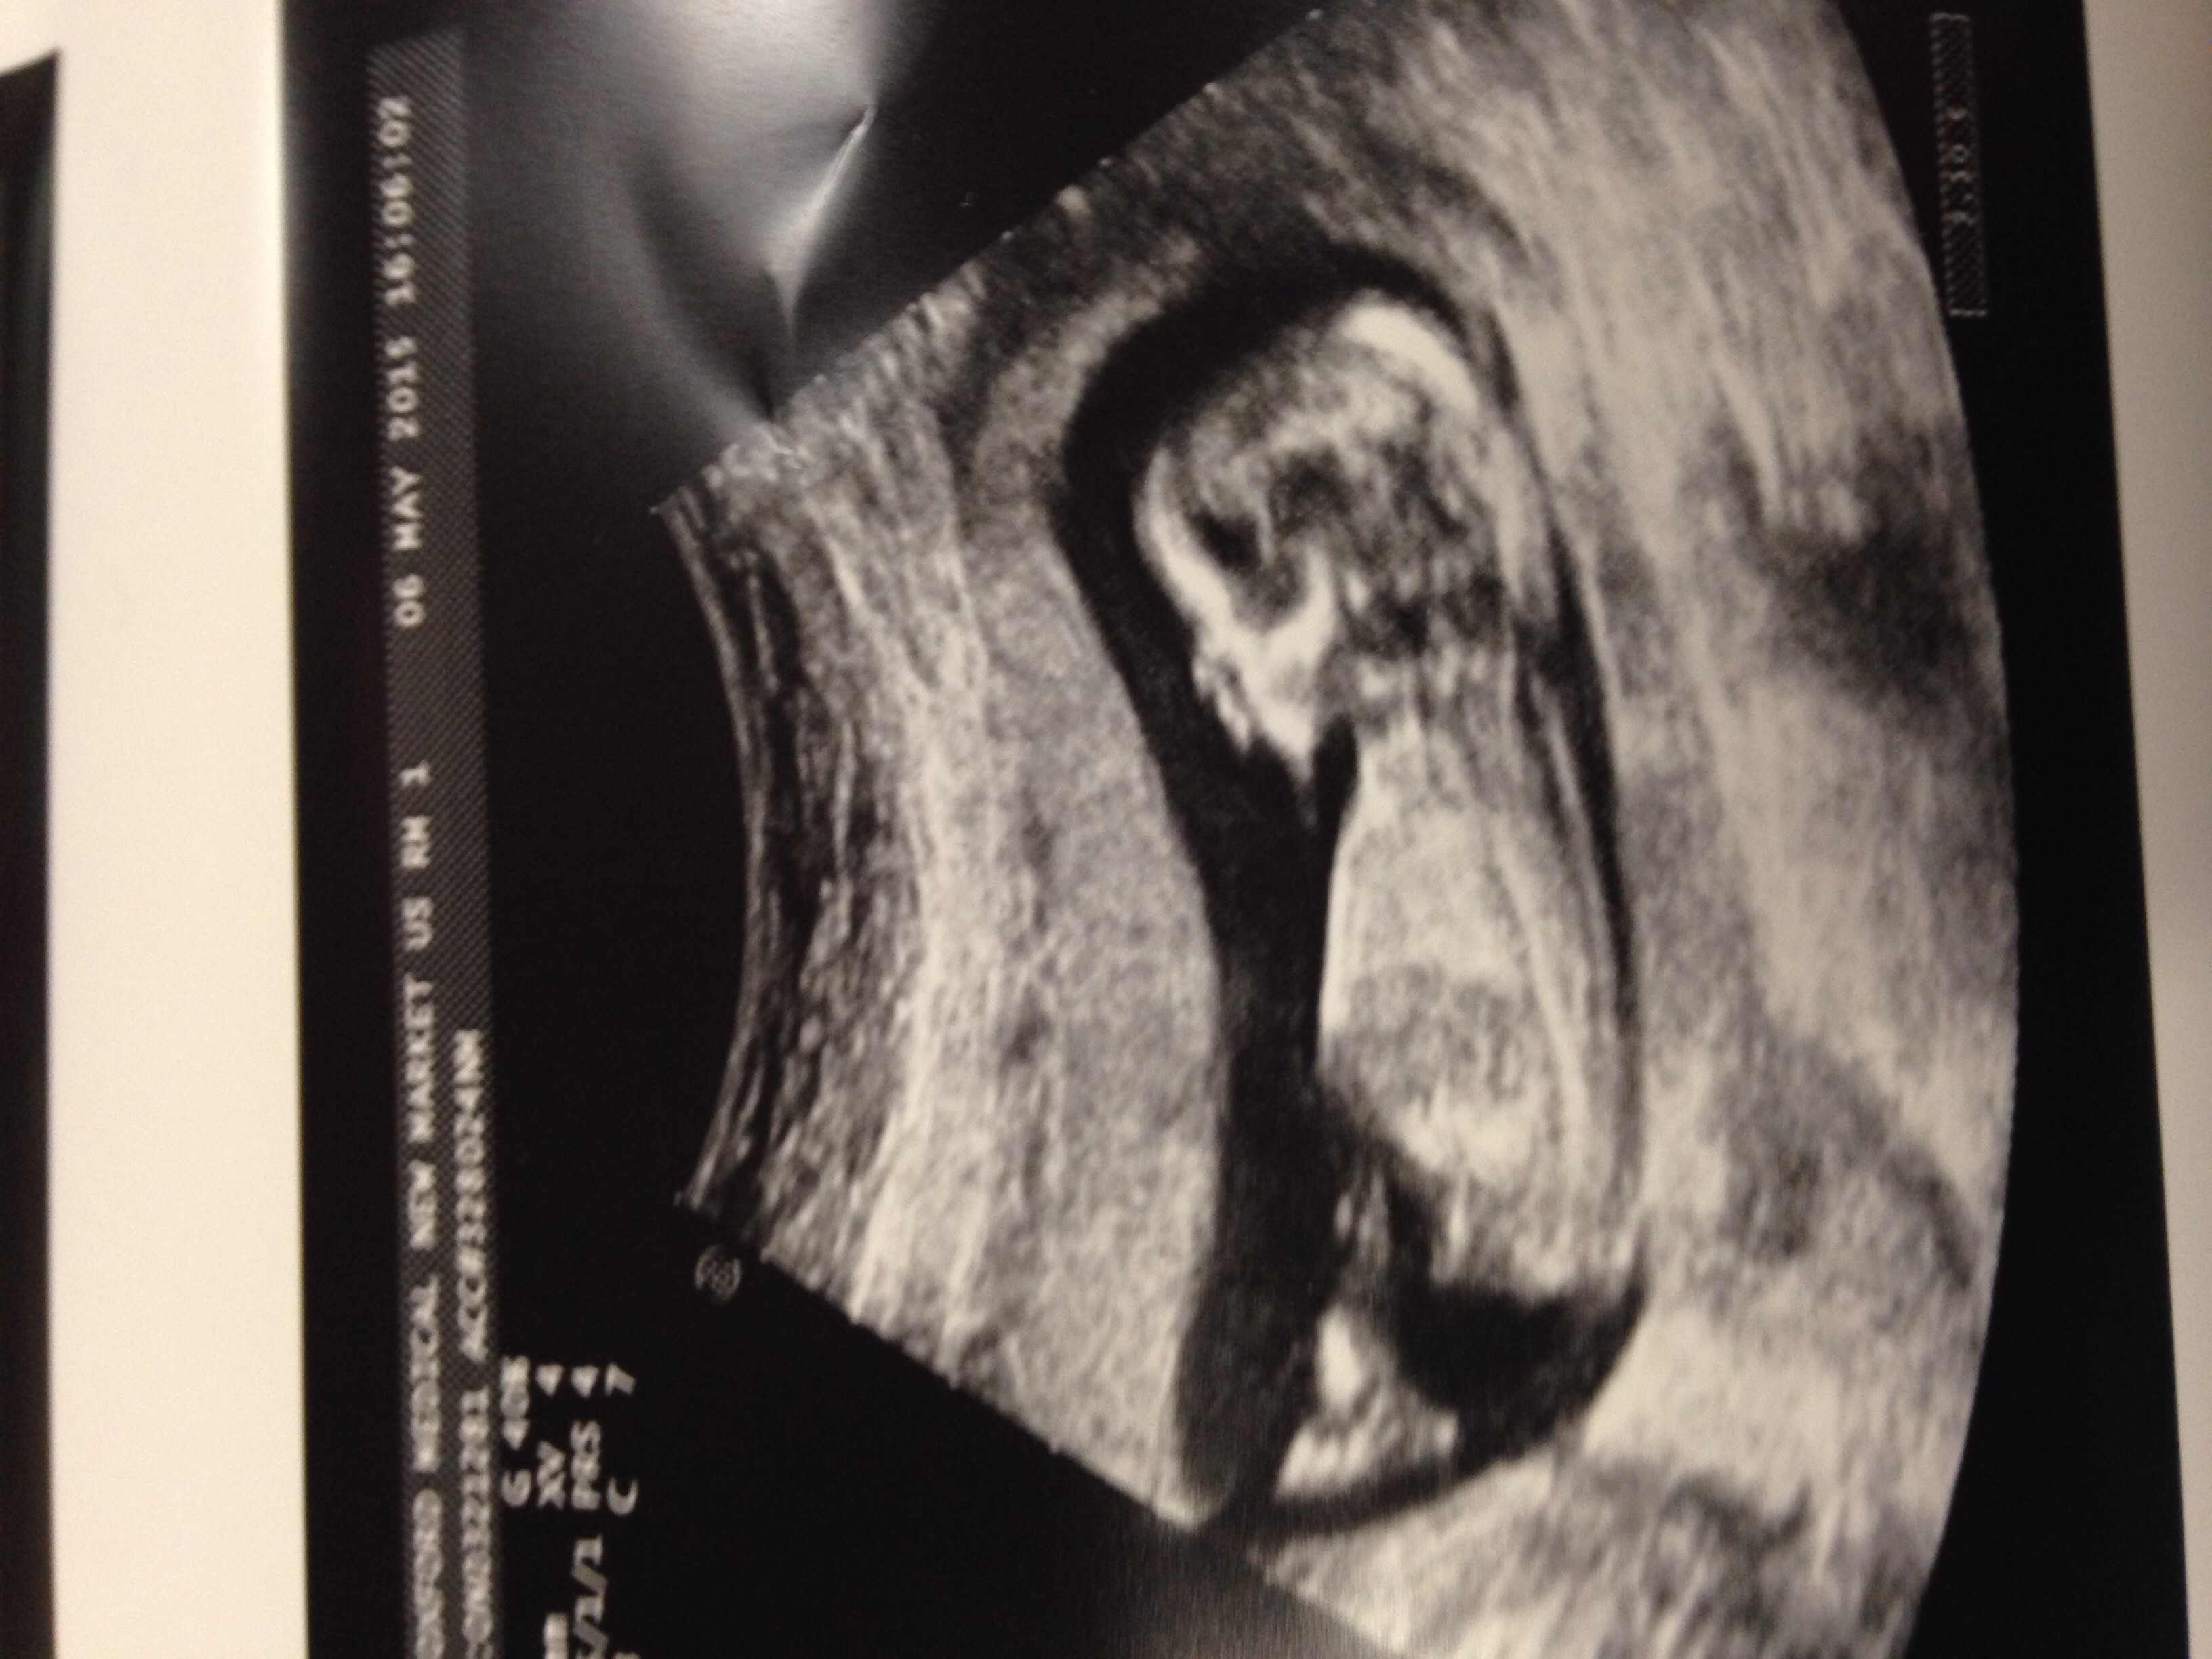

I see boy. Can anyone give any input and please explain your reasoning. I'm so curious :)

Maybe boy, but not sure.

Girly I think!

I'm seeing a girl. What are you hoping for?

Girl I think.

Looks girly to me

Leaning girl also :)

I say girl also.

Thanks for the guesses. I can't wait to find out. I'm having an ultrasound next week. Not sure but I see a pillar and stones.